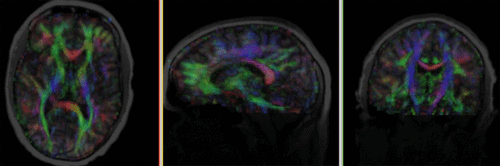

Registration Results

Registered DTI superimposed on T1 registered